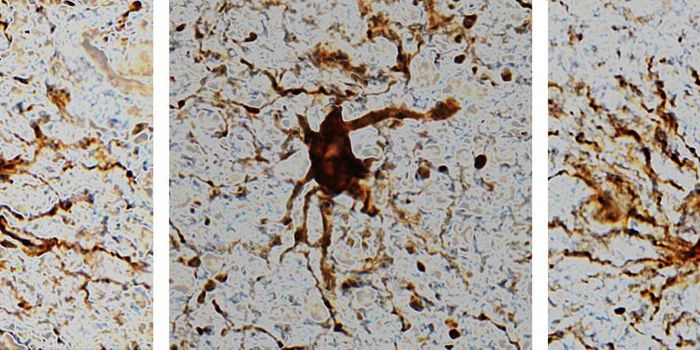

OCT 11, 2021Genetics & GenomicsWhile amyloid plaques are a hallmark of Alzheimer's disease, the neurological disorder has also been linked to inflammat ...